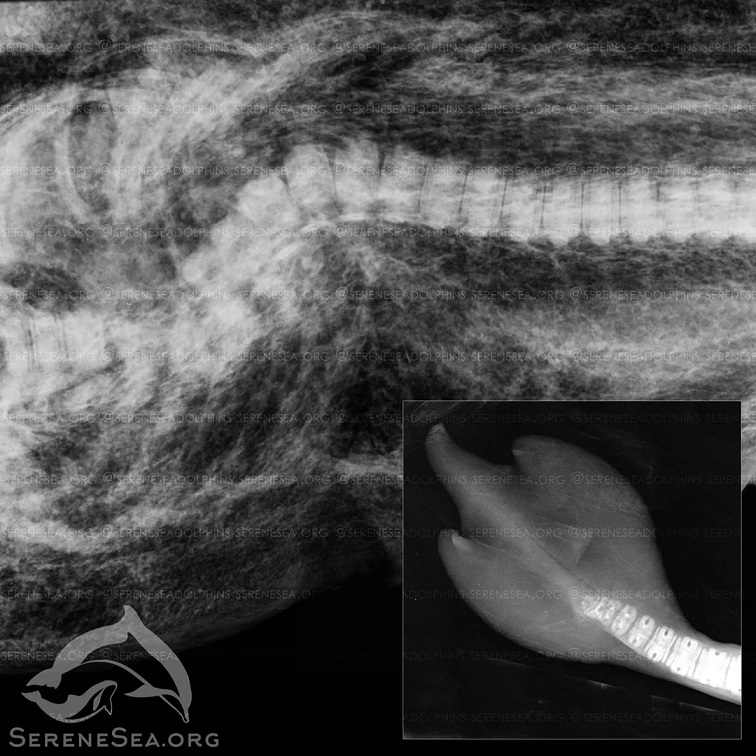

"На рентгенографії, крім особливості будови лопатей, було виявлено зрощення хвостових хребців. Особливості цих двох дельфінів мають схожу природу, - не виключено, що вони є родичами, а вроджена аномалія може бути результатом генної мутації", - відзначили фахівці.

Знайдений біля Алушти дельфін був новонародженим дитинчам. За допомогою рентгенографії у нього виявили перелом хребта зі зміщенням, який він, ймовірно, отримав внаслідок удару дорослого агресивно налаштованого самця. Це і призвело до його загибелі.